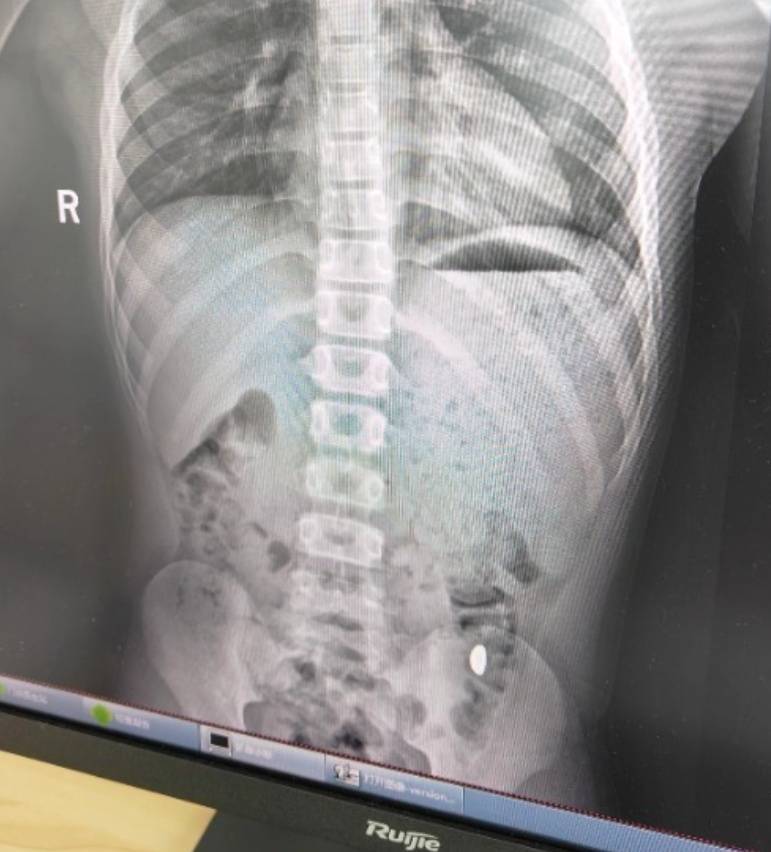

右下加亮点为金豆宝信软件股票。